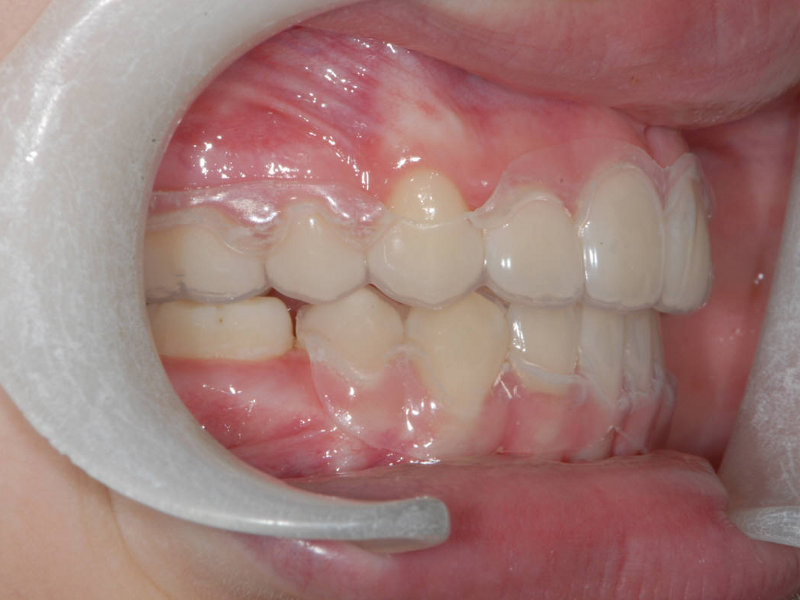

Retentionsplåt med tungavvisare